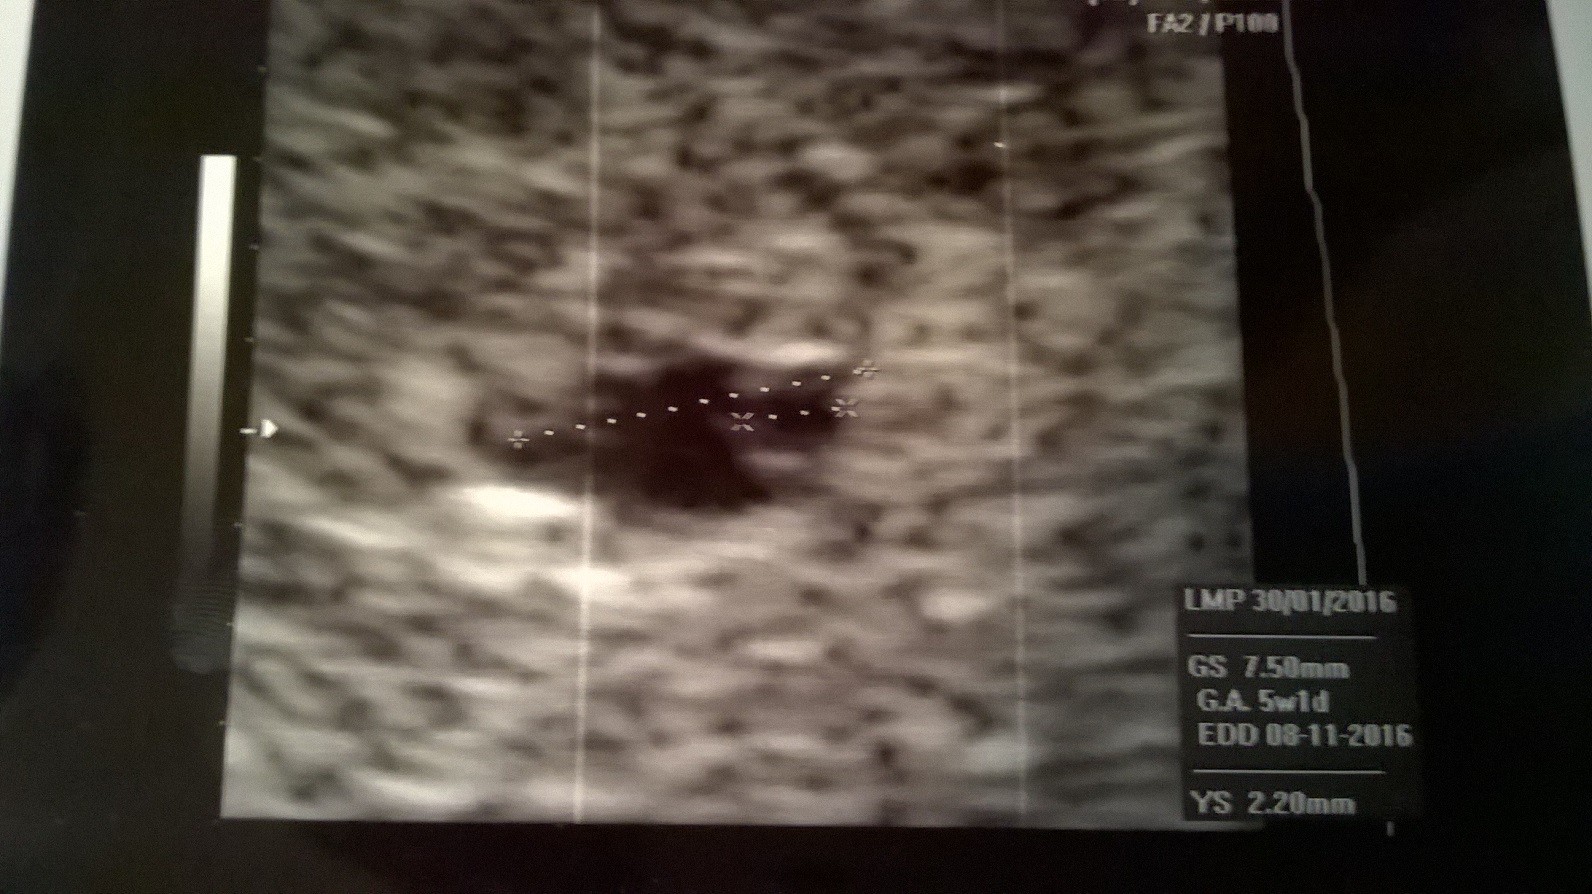

Czy nie powinno być widać coś więcej na zdjęciu ?Zobacz załącznik 750004 Zobacz załącznik 750002